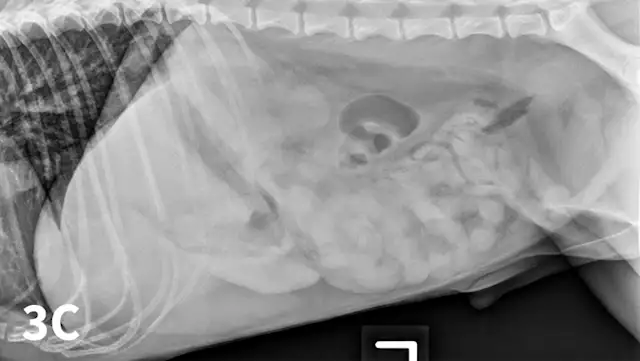

Food or ingesta can look similar to foreign material and can be difficult to differentiate. Depending on the presentation, radiography can be repeated after fasting period to document passage (or lack thereof) of GI content (Figures 3 and 4). Persistence of opaque foreign material in the same location over a 24- to 48-hour period should increase the suspicion of partial obstruction. In cases of complete mechanical obstruction, radiographic features of obstruction can develop during this time. This makes it easier to recognize the obstruction radiographically (Figure 4C).

Left lateral radiograph of a 4-year-old crossbreed dog with a history of vomiting. The patient was clinically stable. Granular, well-defined soft tissue opaque material is present within the fundus of the stomach, consistent with food or foreign material.